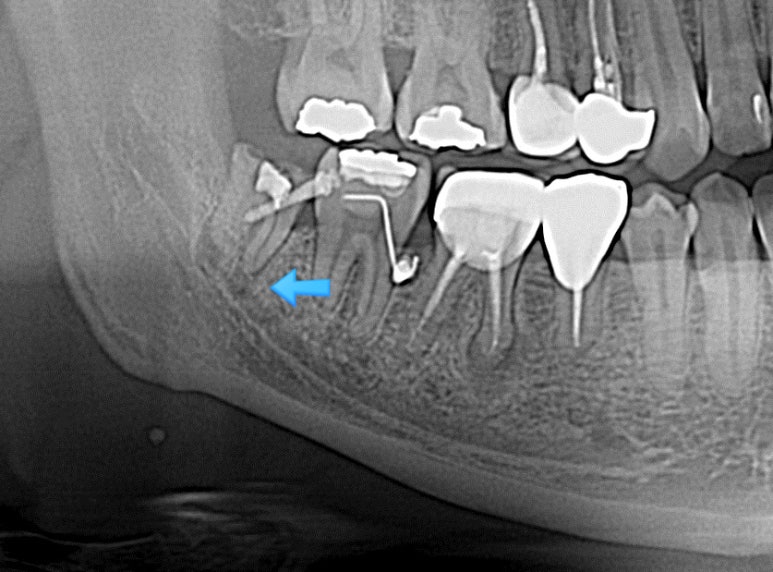

사랑니가 옆으로 누워있고 신경이라 가까워서 큰 병원 가서 뽑으래요~